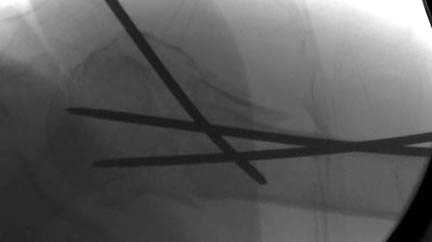

Наш недавний случай перкутанной фиксации "методом

Сиэтла" спицами 2.8 мм с резьбой на конце.